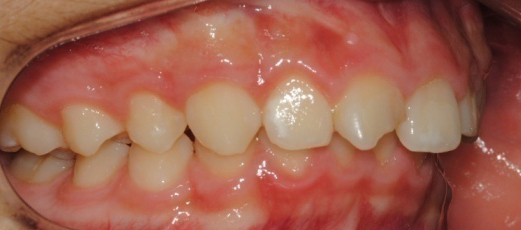

°ú°³±³ÇÕ°ú ¹«ÅÎ,ÅΰüÀýÀ» ÁÖ¼Ò·Î ³»¿øÇÏ¿© ÅμºÀå ¾ÇÁ¤ÇüÀåÄ¡¸¦ ÀÌ¿ëÇÏ¿© Ä¡·áÁßÀΠȯÀÚ·Î Ä¡·á½ÃÀÛ½ÃÁ¡ ±âÁØÀ¸·Î ÇöÀç ۰¡ ¾à 8cmÁ¤µµ ¼ºÀåÇÏ¿´½À´Ï´Ù. (Âü°í·Î 2³âÂ÷ ¿©µ¿»ý°ú ۰¡ 7-9cmŰ Â÷À̳²)